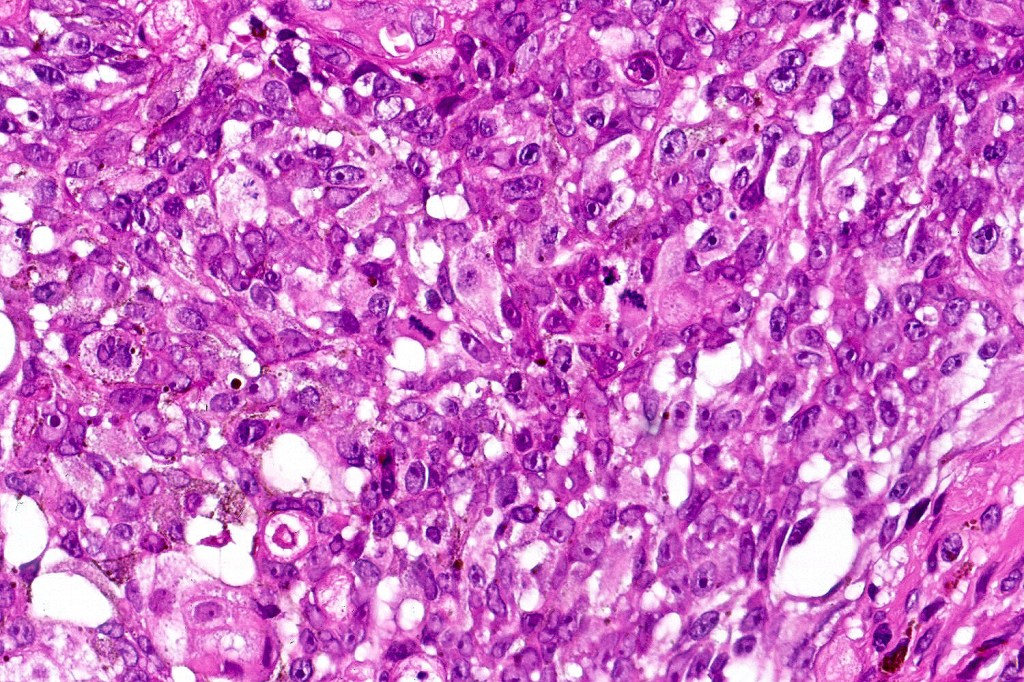

Immunohistochemistry (images from Professor Wayne Grayson’s case)

•Beta-catenin, P-cadherin, E-cadherin +ve

•AE1/AE3 (image1), CK5/6 positive

•Dendritic cells S100 (image 2), Melan-A, HMB45 +ve (image 3),